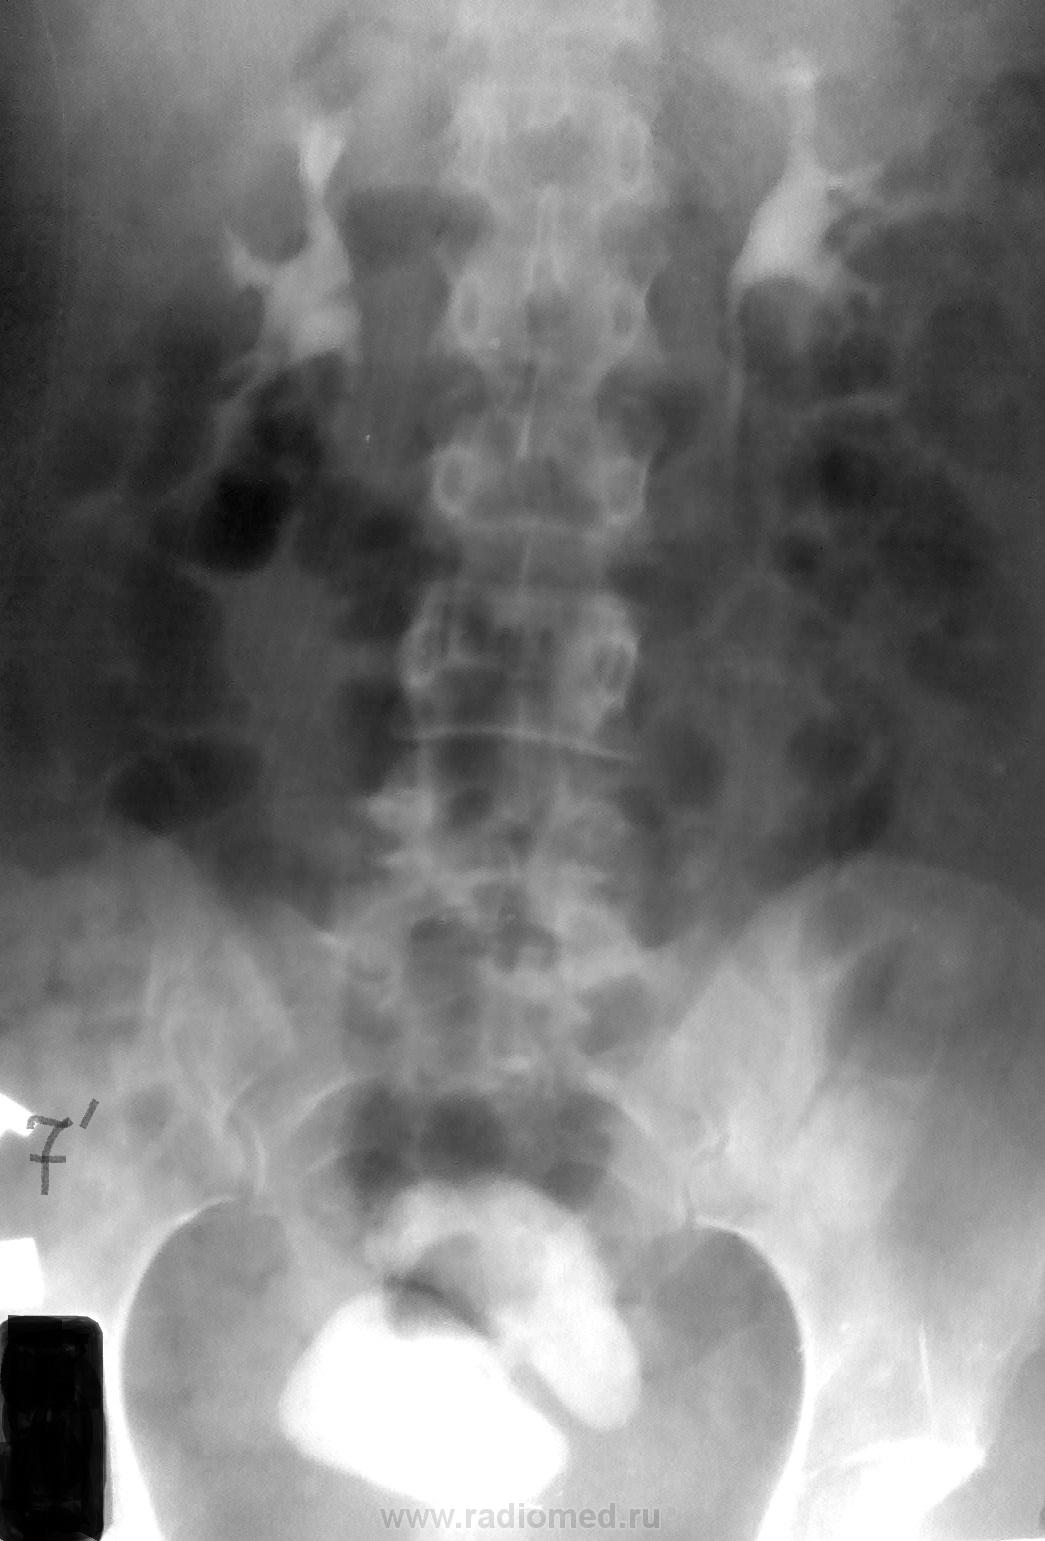

Попал мне тут в руки один "шедевр"

Качество снимков не особое, но не в этом суть)))

Вариант 1 - фистула

Вариант 2.

Внутривенная урография произведена после исследования пищеварительной трубки.

Видать не просто так обзорный отсутствует...

Вариант 3.

Теоретически допустимо, что один из мочеточников открывается в прямую кишку, такие случаи в литературе описаны.

Валентин Львович, логика у вас - железная, так оно и было - исследование ЖКТ за два дня до этого, вот что может быть, когда урологи настаивают проводить исследование БЕЗ ОБЗОРНОЙ, а так то -  и сам на первом этапе о фистуле "размечтался", но не там то было...ларчик открылся просто))))